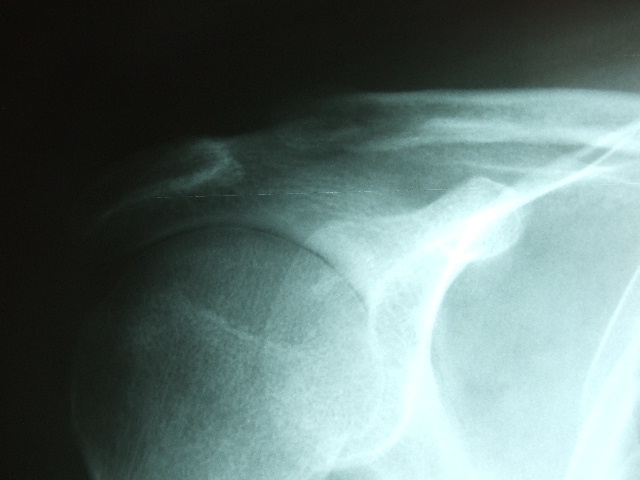

Fractura de húmero, intensa desviación de fragmentos